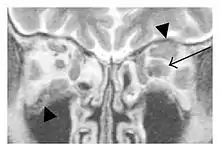

Swelling of the left superior and lateral rectus muscles, a mass lesion around the left optic disc (arrow), and enlargements of the left supraorbital nerve and the right infraorbital nerve (arrow heads) in a 60-year-old man with a serum IgG4 of 463 mg/dL.[1] (T1-weighted MRI)

Bilateral supraorbital nerve enlargements (arrows) and right infraorbital nerve (arrow head) enlargement in a 47-year-old woman with a serum IgG4 of 1000 mg/dL.[1] (T1-weighted MRI)